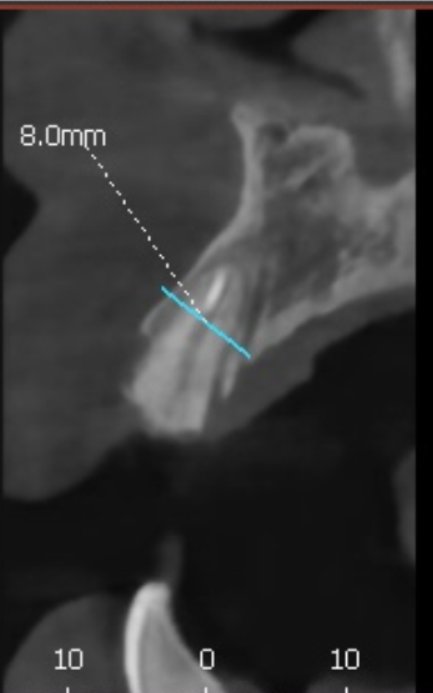

저희는 환자분들의 정확한 상태를 파악하기 위해

3D CT를 아주 꼼꼼하게 돌려보며 진단해요.

실제로 뼈이식이 꼭 필요한 부위인지,

아니면 남아있는 뼈만으로도 충분한지를

화면을 함께 보며 상세히 설명해 드립니다.

이번 환자분의 경우에도 CT를 분석해 보니

다행히 뼈의 폭이 5mm~7mm 정도로

충분히 두꺼웠습니다.

뼈의 폭이 충분하다면

굳이 뼈이식을 할 필요가 없습니다.^^